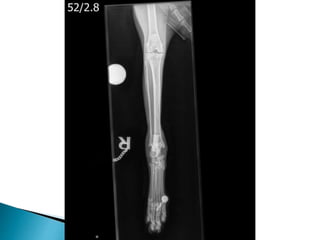

 Radiographs ***

 Radiographs

 Viral Testing- negative  Joint Culture  Cytology  Radiographs ***  Ultrasound Abdomen

• #10 He had smooth recovery from anaesthesia and seemed much more comfortable on his methadone. Cytology and Culture both were negative. Hocks and elbows to have increased WBC, predominately neutrophilic inflammation (91- 94%). Mild toxic change to the neutrophils. The right and left stifle: Low Neutrophils (< 1 x10e9/l). The majority of cells present were large mononuclear cells (85 - 87%). Immune mediated hypersensitivity type III reaction. Run through the types… I = hay fever idea – IgE released. II = IMHA like whereby antibody binds to cell surface antigen III = Antibody binds to cell suface antogen however these are solvent in blood and not attached to cells and so can settle out in various locations throughout the body. Periosteal proliferative polyarthritis occurs most often in male cats (intact and castrated), but female cats can also be affected. Cats of any age can develop this polyarthritis, but it is most common in young adults. Affected cats experience fever, lethargy, a stiff gait, and joint pain and swelling, particularly of the carpus and hock. There is sometimes concurrent edema of the skin and soft tissues overlying the joints. Lymph node hyperplasia may cause severe regional lymphadenopathy. Synovial fluid analysis reveals a moderate-to-severe neutrophilic pleocytosis and culture is negative. Papers form the 1980’s actually found that 100% of cats with chronic progressive arthritis showed FSFV or antibodies to it. But is it just incidental because this virus in particular is found in normal cats also. It has been suggested that infection with FeLV or FIV-induced immunosuppression allows FeSFV to multiply in the joints of predisposed individuals. However in papers that I came across, surprisingly there isn't an increased incidence of FeLV or FIV in affected cats. It occurs more commonly in young, entire or castrated, male cats less than 5 years of age. Radiographic changes may not be evident for the first 10–12 weeks of illness and then early findings include periarticular soft tissue swelling and mild periosteal proliferation. This matache Koshka to a T being that after roughly two months of steroid effectiveness. An abnormally coarse trabecular pattern of the bones of affected joints. Over time, the periosteal proliferation worsens and extends beyond the confines of the joint, which may lead to ankylosis. Periarticular osteophytes, subchondral cyst-like lesions and periarticular erosions are evident. Calcification and erosion of bone may occur at the attachment of ligaments and tendons, causing painful lesions (enthesopathies).